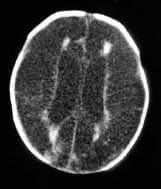

La TAC cerebral (Fotos 3, 4 y 5), muestra alteración difusa en la densidad de la corteza y la sustancia blanca en relación con degeneración quística vista en pacientes con hidranencefalia severa, se conserva la densidad de los territorios de la circulación posterior; se toma resonancia magnética cerebral (Foto 9), siendo los hallazgos compatibles con hidranencefalia, sin signos de hipertensión endocraneana. Por el estado clínico del paciente se considera continuar seguimiento ambulatorio por neuropediatría, neonatología y pediatría.